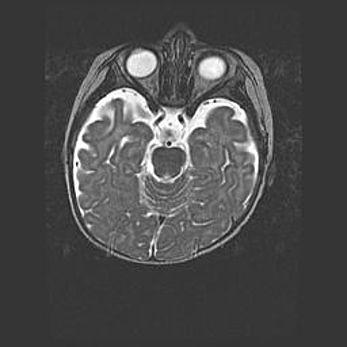

Сообщающаяся гидроцефалия. Кистозная энцефаломаляция головного мозга.

Возраст: 3 месяца 4 дня

Вес: 3100 г

Пол: женский

Окружность головы: 34 см

Срок гестации: 31 неделя

Кистозная энцефаломаляция головного мозга - одна из форм поражения головного мозга в детском возрасте. Характеризуется возникновением множественных и распространённых кист в коре, белом веществе и подкорковых образованиях головного мозга у плодов, новорождённых и детей раннего возраста. Развитие кистозной энцефаломаляции связано с внутриутробной асфиксией и гипотонией, родовой травмой, тромбозом синусов, пороками развития сосудов, инфекциями, сепсисом и другими причинами. Наиболее значимые инфекционные агенты: вирусы простого герпеса, цитомегалии, краснухи, токсоплазмы, энтеробактерии, золотистый стафилококк и другие.